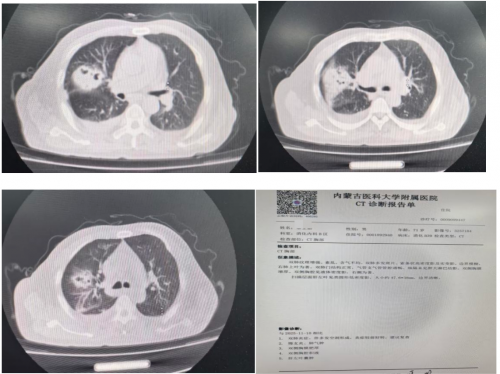

胸部CT变化:

11月10日:

11月19日: